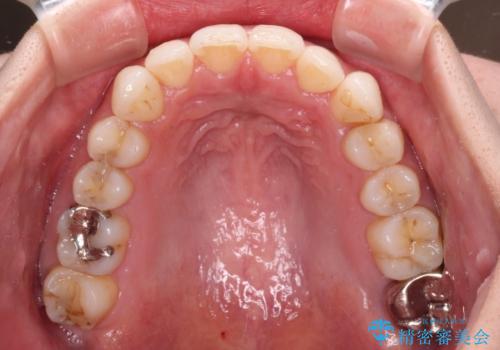

- 上下の前歯のデコボコを治したいとのことで来院された患者様です。

上下顎ともにIPR(歯と歯の間を削る)と歯列全体の拡大によって叢生が解消するように設計し、インビザラインにより治療を行うこととしました。